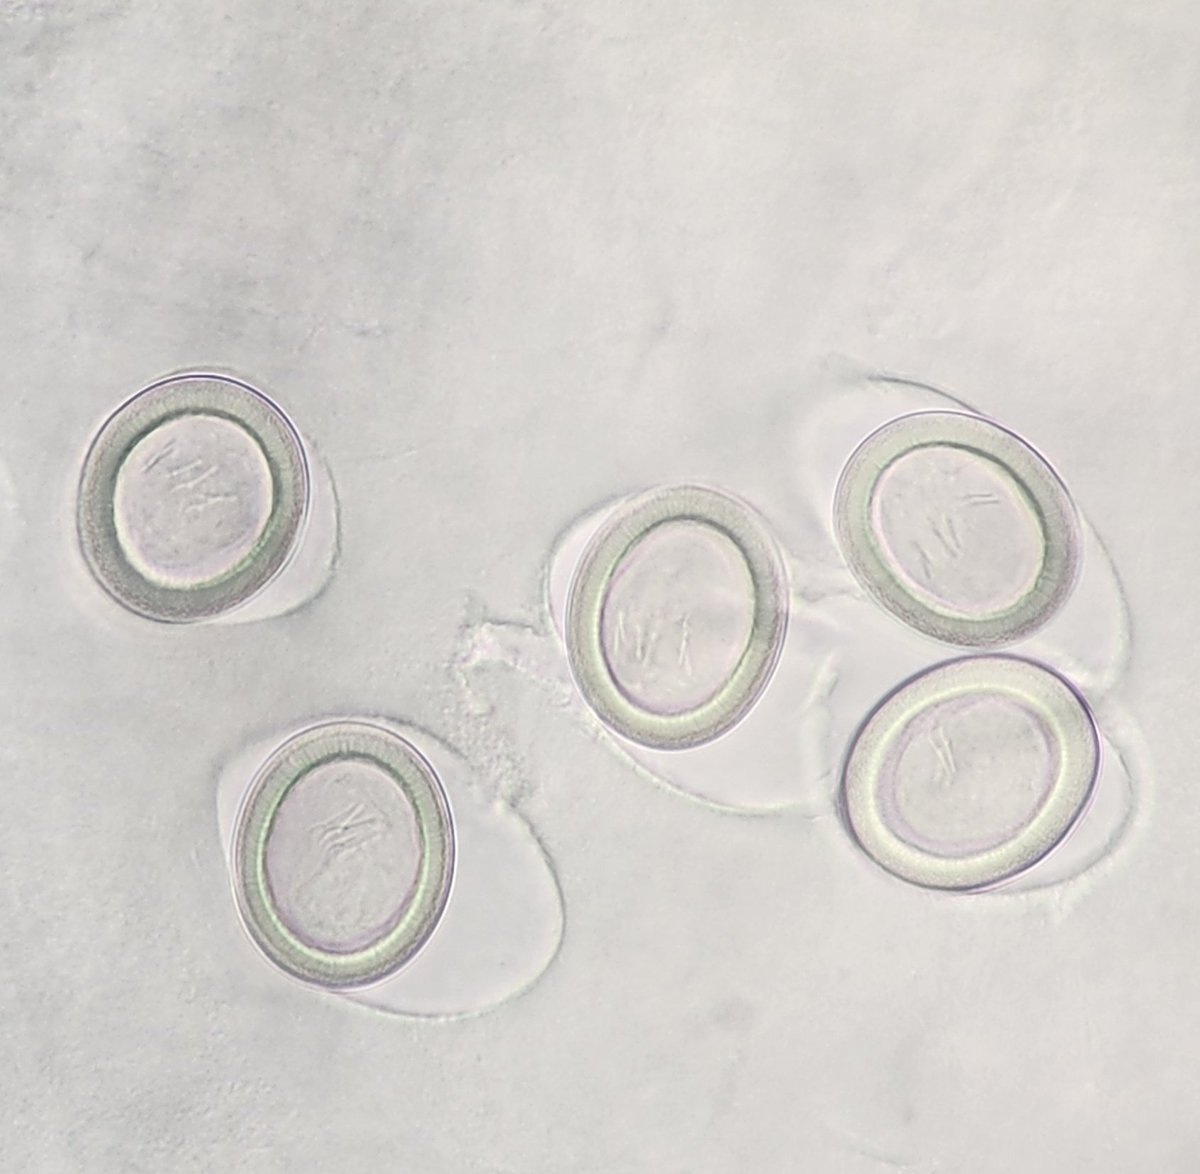

This is amazing and cool to see. Admittedly, I have not seen this often at all. Continued development of embryos in Ascaris eggs...in fixative! Talk about resilient πŸͺ±! #parasitology Bobbi Pritt, MD ARUP Laboratories

This is amazing and cool to see. Admittedly, I have not seen this often at all. Continued development of embryos in Ascaris eggs...in fixative! Talk about resilient πŸͺ±!

#parasitology

<a href="/ParasiteGal/">Bobbi Pritt, MD</a> <a href="/ARUPLabs/">ARUP Laboratories</a>